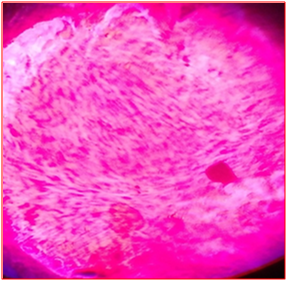

Figure 8 Ductal carcinoma in situ HPE, H&E x10.

Figure 9 Ductal carcinoma in situ on frozen section X10.